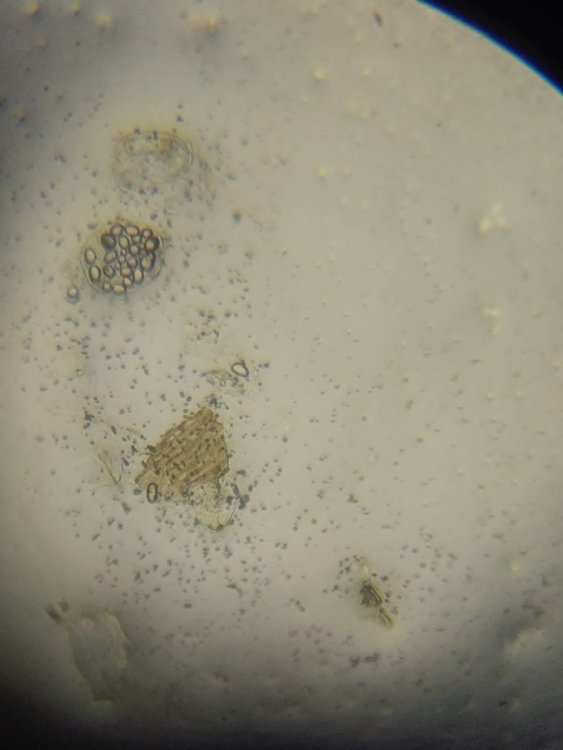

1. Фото крахмал (кружочки) - голубь

2. Фото онкосферы(яйца цепень)- вороны